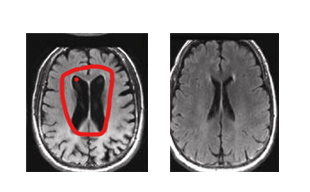

“여기 보시면, 왼쪽이 한 달 전 사진이고, 오른쪽이 오늘 찍은 사진입니다. 정상 뇌와 비교하면 아직 검은 부분이 많지만, 한 달 전보다 확연히 줄어든 것을 볼 수 있습니다.”

화면 캡처 2025-09-22 122418.png 왼(한 달 전 사진), 오(정상 사진)

화면을 바라보자, 의사의 말대로 한 달 전 사진의 검은 공간이 줄어들어 있었다. 하지만 여전히 빈 곳이 남아 있었다.

“이 정도까지 치유되는 경우는 저도 처음 봅니다. 열심히 노력하신 결과가 분명하네요. 지금 상태라면, 짧게는 3일, 길게는 4일 정도는 기억이 유지될 것 같습니다.”